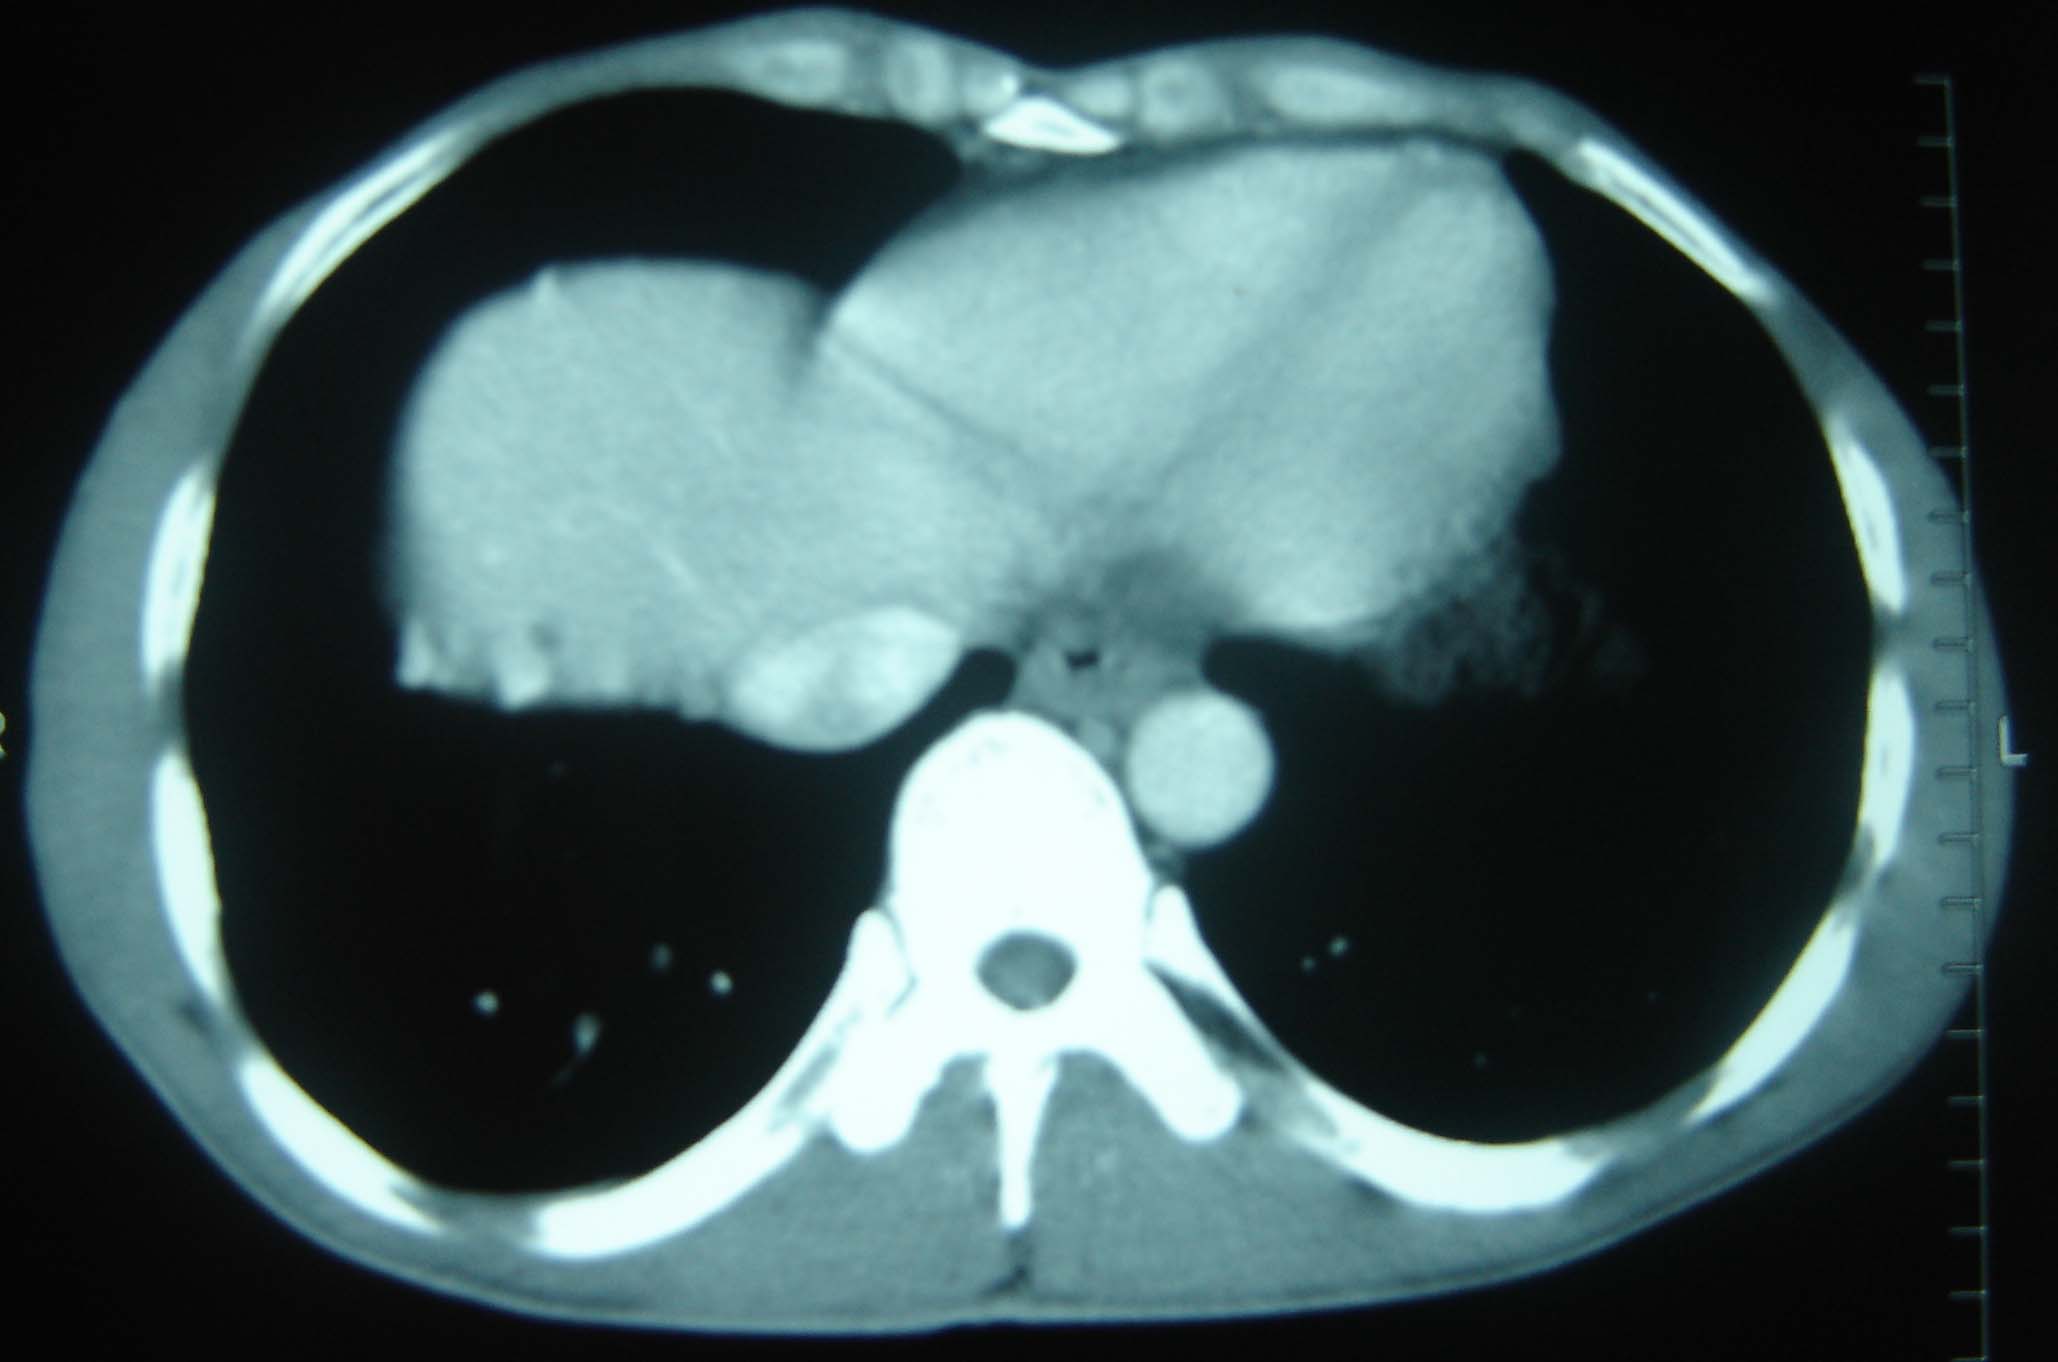

标题: CT25321:两肺多发结节 请会诊 [打印本页]

标题: CT25321:两肺多发结节 请会诊

男 、43岁,咳嗽胸痛,装修工,平时接触粉尘较多,有吸烟史10多年,纤维支气管镜检查未发现异常,胃镜、腹部b超检查亦未发现异常,颈部淋巴结活检未发现肿瘤细胞。

1)考虑双肺及胸膜多发性转移瘤。2)肺气肿。